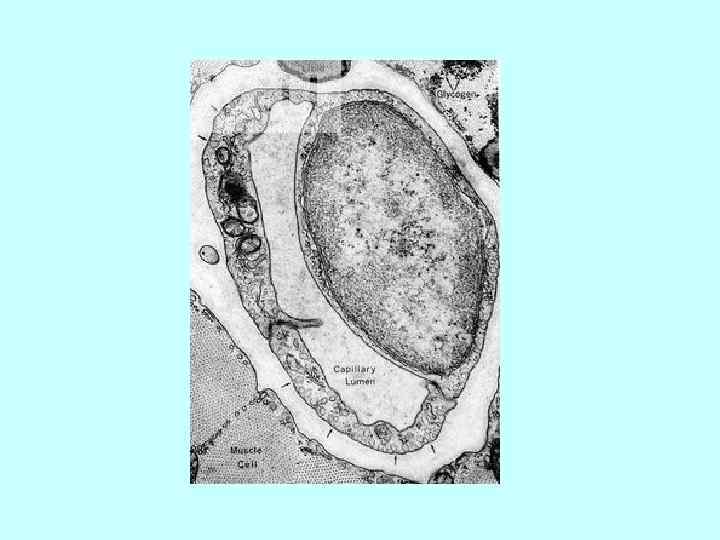

Бедренная артерия кошки 1. внутренняя оболочка (tunica interna) 1. 1. эндотелий; 1. 2. субэндотелиальный Бедренная артерия кошки 1. внутренняя оболочка (tunica interna) 1. 1. эндотелий; 1. 2. субэндотелиальный слой; 1. 3. внутренняя эластическая мембрана 2. средняя оболочка (tunica media), и в ней: • 2. 1. гладкие миоциты; • 2. 2 эластические волокна 3. наружная оболочка (tunica externa), и в ней; • наружная эластическая мембрана • 3. 2 сосуды сосудов (vasa vasorum)